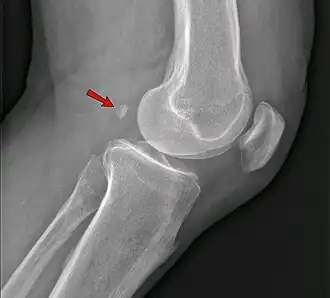

The fabella is a small sesamoid bone found in some mammals embedded in the tendon of the lateral head of the gastrocnemius muscle behind the lateral condyle of the femur. It is an accessory bone, an anatomical variation present in 39% of humans.[1][2] Rarely, there are two or three of these bones (fabella bi- or tripartita). It can be mistaken for a loose body or osteophyte. The word fabella is a Latin diminutive of faba 'bean'.[3]